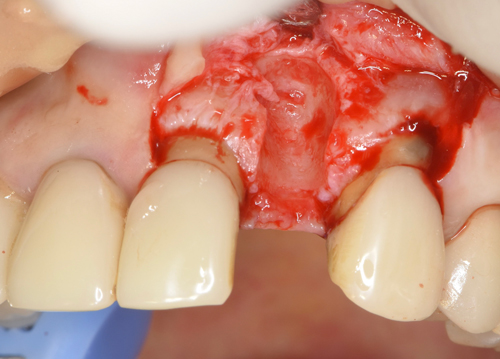

抜歯した歯根の先端には肉塊の腫瘍が一緒に付着していました。どんどん骨が溶けていく根源です。

腫瘍摘出ドリルで骨に付着している肉塊を徹底的にはく離させます。

唇側の半分がほとんど骨が失われていました。この状態からインプラントを移植して、不足している骨も同時に再生定着

させていきます。